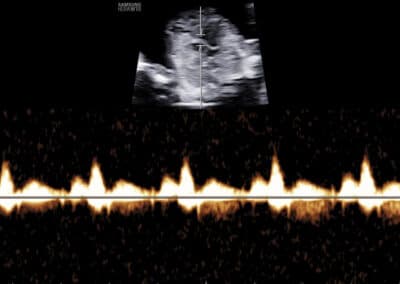

Dopplerovské vyšetření ductus venosus – normální nález (pozitivní a-vlna s PI do 1.3)

Dopplerovské vyšetření ductus venosus – abnormální nález (reverzní a-vlna s PI nad 1.3)

UZ vyšetření průtoku v ductus venosus dle FMF protokolu

Podmínky FMF certifikace pro vyšetření průtoku krve v ductus venosus:

FMF certifikát na vyšetření NT (včetně absolvování on-line kurzu o vyšetření v 11.-14. týdnu těhotenství před získáním tohoto certifikátu) Úspěšné složení krátkého on-line testu týkajícího se hodnocení snímků zobrazujících vyšetření ductus venosus Zaslání tří snímků ze správného vyšetření ductus venosus

Protokol pro správné Dopplerovské vyšetření průtoku krve v ductus venosus:

CRL 45-84 mm (11-13+6 týden) Vyšetření musí být provedeno během klidové fáze (absence pohybů) plodu Zvětšení (hrudník a břicho plodu vyplňují většinu obrazovky) Mid-sagitální řez tělem plodu, barevné Dopplerovské zobrazení toku krve v pupečníkové žíle, ductus venosus a v srdci Gate 0.5-1mm přes ductus venosus (místo aliasingu – světlé barvy při Dopplerovském vyšetření) Odklon průběhu v ductus venosus 0-30º od vertikální osy Nízký filtr (50-70 Hz) Vysoká rychlost posunu křivky (2-3cm/s)